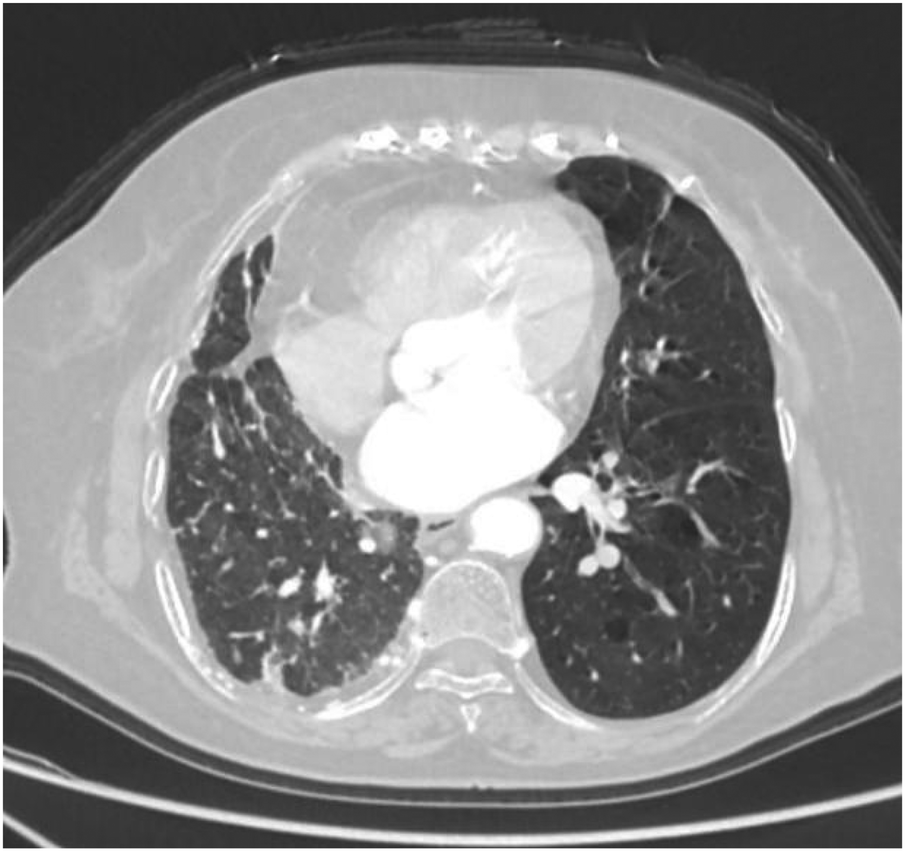

Thoracoabdominal aortic CTA and chest CT findings are illustrated in Figures 1–14. There was no evidence of aortic dissection. The right pulmonary artery was absent distal to approximately 3 cm from the bifurcation, with a smooth and rounded defect margin. The main pulmonary artery and its major branches showed no abnormal densities. No right pulmonary artery branches were observed in the right lung. Multiple tortuous arterial branches from the right subclavian artery, descending aorta, and right renal artery supplied the right lung. The right hemithorax was smaller, with localized pleural thickening and adhesions bilaterally. Multiple bronchiectasis with thickened walls and patchy, nodular, and linear opacities encircled the right lung. Increased translucency and several hyperlucent regions were visible in the left lung. CT imaging findings demonstrated: 1. Congenital absence of the right pulmonary artery (RPA), with the right lung supplied by collateral circulation originating from the right subclavian artery, right intercostal arteries, and the right renal artery. 2. Right pulmonary hypoplasia, bronchiectasis of the right lung, accompanied by infection and partial consolidation in the right upper lobe, compensatory hyperinflation of the left lung, and multiple bullae in the left lung. 3. Bilateral localized pleural thickening and adhesions. 4. Osteoporosis and mild flattening of the T6 vertebra and compression fractures of T11 and T12.

Figure 11

Axial image shows partial bronchiectasis in the right lung, partial inflammation and linear opacities in the right lung, thickening of the right pleura, and rightward shift of the trachea and mediastinum.

Figure 12

Axial image shows pulmonary emphysema in the left lung with multiple bullae.

Figure 13

Coronal image shows narrowing of the right thoracic cage and right lung, bronchiectasis in the upper lobe of the right lung with surrounding inflammation.

Figure 14

Coronal image shows bronchiectasis and inflammation with consolidation in the upper lobe of the right lung, thickening of the right pleura, and pulmonary emphysema in the left lung.